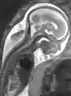

A magnetic resonance image of a fetus in utero